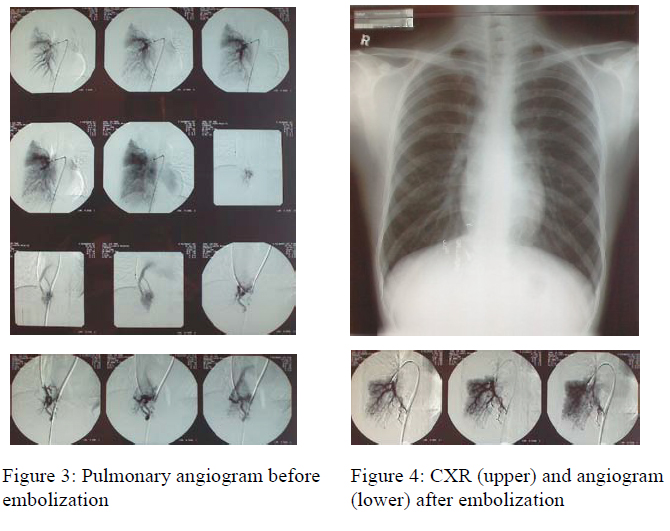

He was then referred to Queen Elizabeth Hospital for further management. Pulmonary angiogram was performed and showed four AVMs at right lower lobe. In addition, multiple fine nodularities were noted at background of right lung parenchyma, features probably due to very fine tiny AVM and were not embolizable. These 4 AVMs at right lower lobe were embolized with platinum coils and post embolization angiogram showed satisfactory occlusion (Fig. 3 & 4). Fig. 5 showed the CXR after embolization.

After treatment, his exercise tolerance was similar. Orthodeoxia was still present with SaO2 92% RA while sitting and 95% RA when lying. His Hb level was 18.3g/dL. His calculated shunt fraction was 17.1% (normal 5%). The seemingly unimproved symptoms and laboratory findings of the patient could probably be explained by the presence of multiple tiny non-embolizable AVMs in the right lung parenchyma as mentioned above.